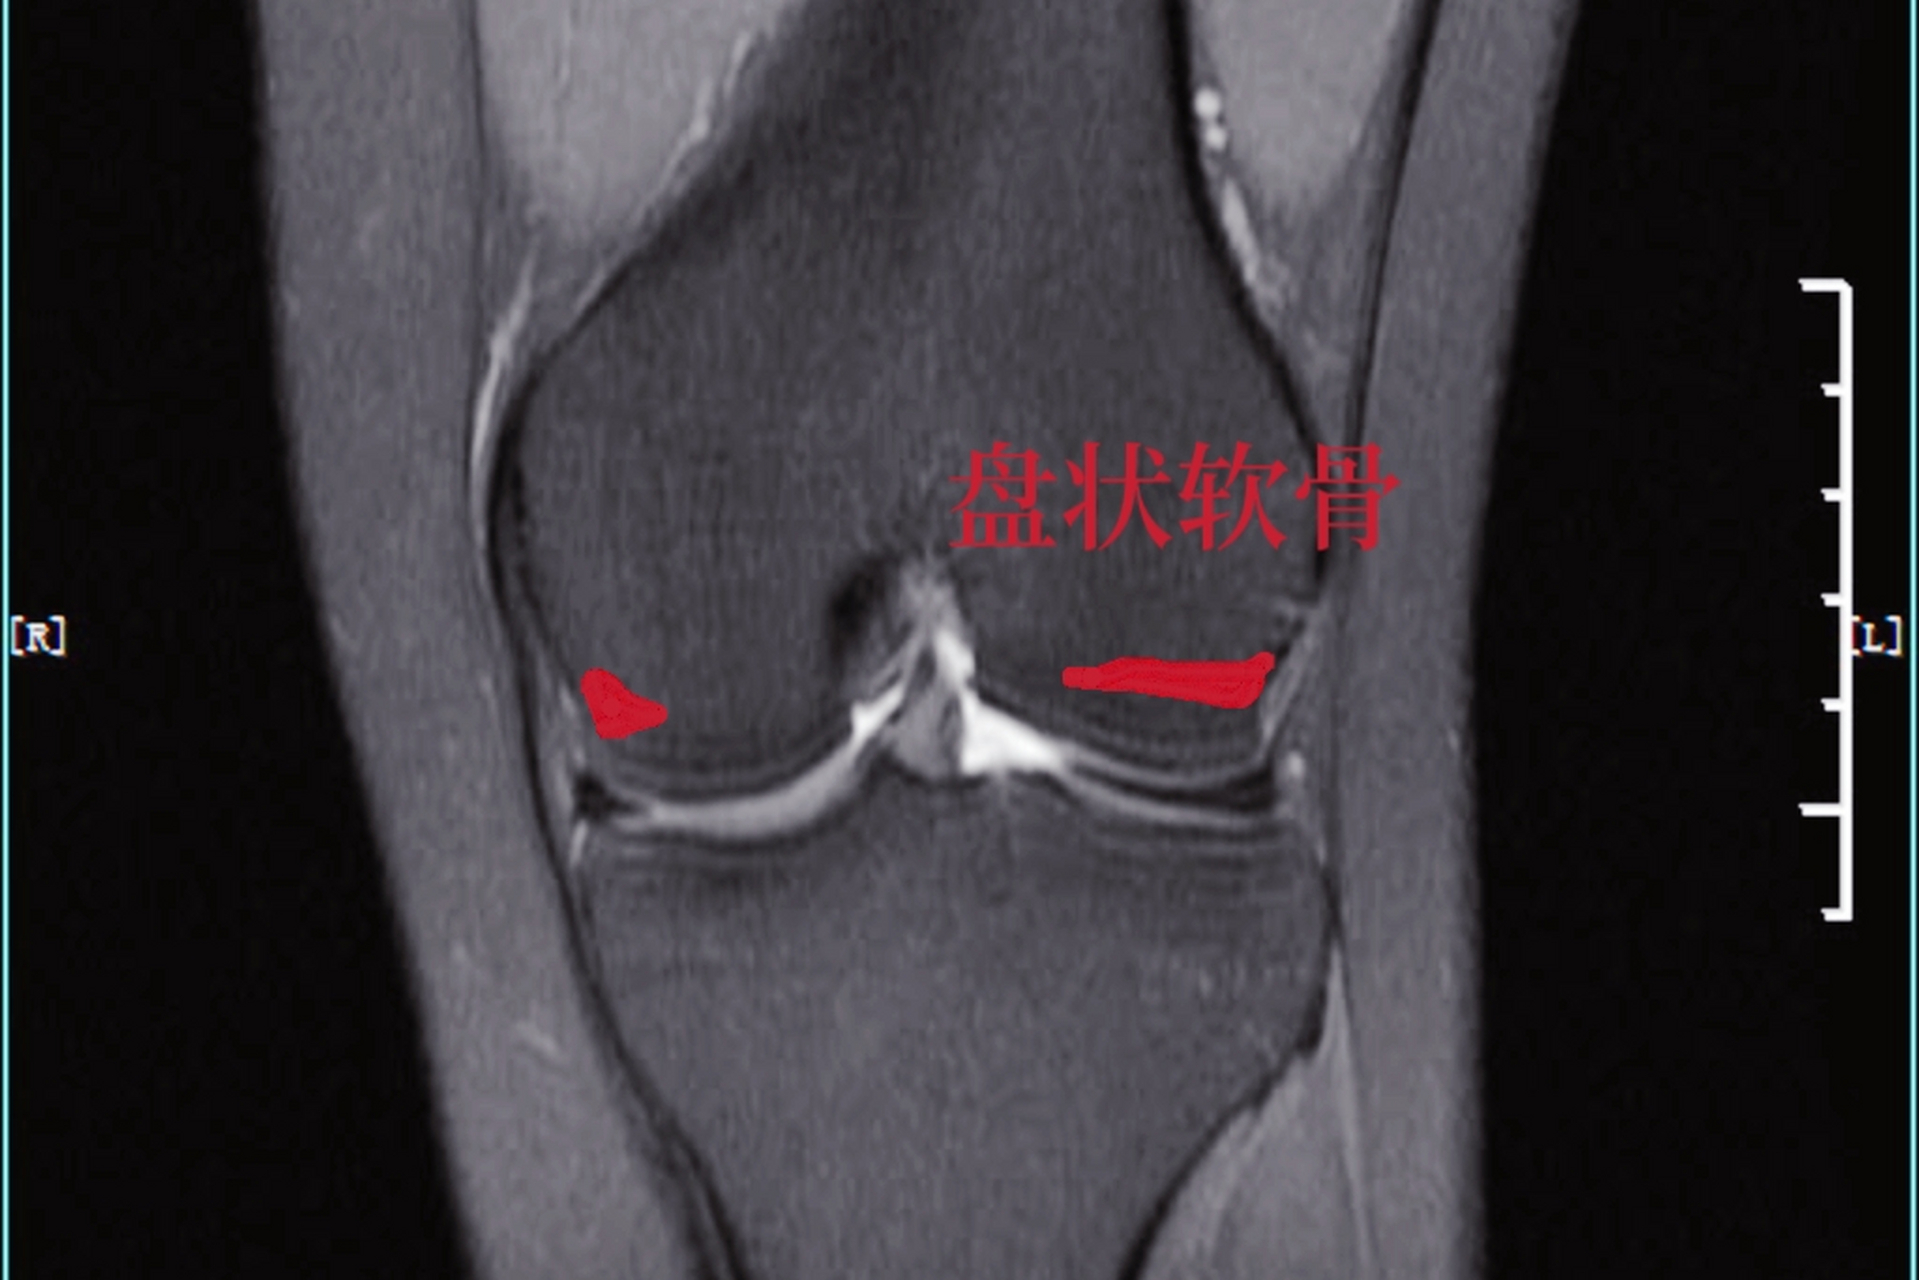

半月板的常见病变及正常变异的mri诊断